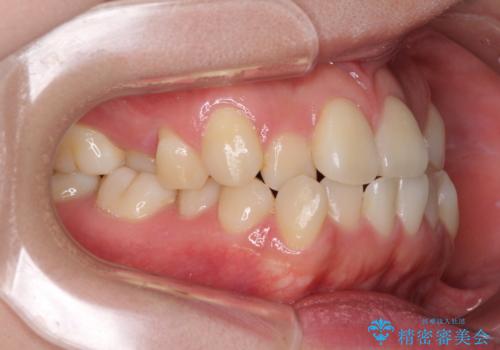

骨格的に下顎が前方位の受け口傾向であり、それが原因でクロスバイトとなっていました。

なお、右奥の歯が180度回転した状態で萌出しており、こちらは改善困難なため、そのままの向きで配列することとしました。

右奥の歯が180度回転していることで、噛む度にワイヤーに無理な力がかかったようで、頻繁にワイヤーが切れてしまいました。また、下顎を後方に移動させるためのアンカースクリューも脱離することが多く、治療期間が長くなってしまいました。